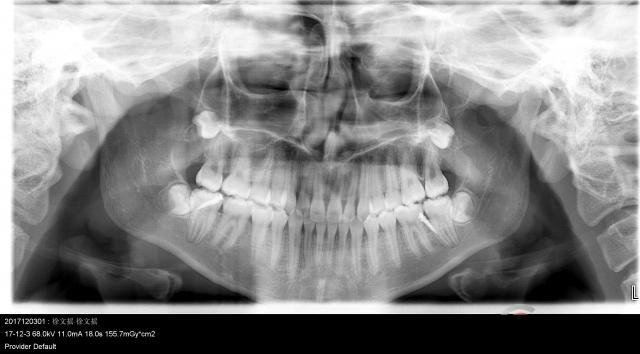

*牙齿

孩子出牙时间的早晚和顺序,主要是由遗传因素所决定的,没有太多规律。通常来说,8~34个月是乳牙萌出的时期。乳牙有20颗,而恒牙有32颗。此外,乳牙的牙釉不厚,没有恒牙结实,因此更容易长龋齿。

提醒:

在孩子很小的时候就要教会他正确的刷牙方法,而且要选择符合他年龄的牙刷和牙膏。尽管很多孩子觉得练习刷牙很好玩,但是也要注意,不要让他养成吞牙膏的习惯,尤其是含有氟的牙膏。